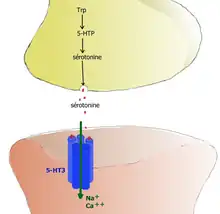

- récepteurs ionotropes : les récepteurs 5-HT3 sont des récepteurs canaux à perméabilité cationique. Leur stimulation provoque une entrée d'ions sodium Na+ et calcium Ca2+ qui diminuent rapidement la charge négative intracellulaire (soit une dépolarisation) du neurone postsynaptique et déclenchent un potentiel d'action postsynaptique excitateur (PPSE). Ils sont donc excitateurs.

- 5-HT3 → entrée de Na+ et Ca2+ → dépolarisation → potentiel d'action PPSE.

- Ces récepteurs 5-HT3 sont situés sur l'extrémité des fibres sensitives extrinsèques vagales et splanchniques. Leur stimulation envoie un signal par la moelle spinale jusqu'au centre de contrôle du vomissement qui induit une sensation de nausée et provoque le vomissement. Les antagonistes sélectifs du récepteur 5-HT3 de la famille des sétrons sont utilisés pour combattre les nausées et vomissements postopératoires ou ceux induits par les traitements anticancéreux[25].